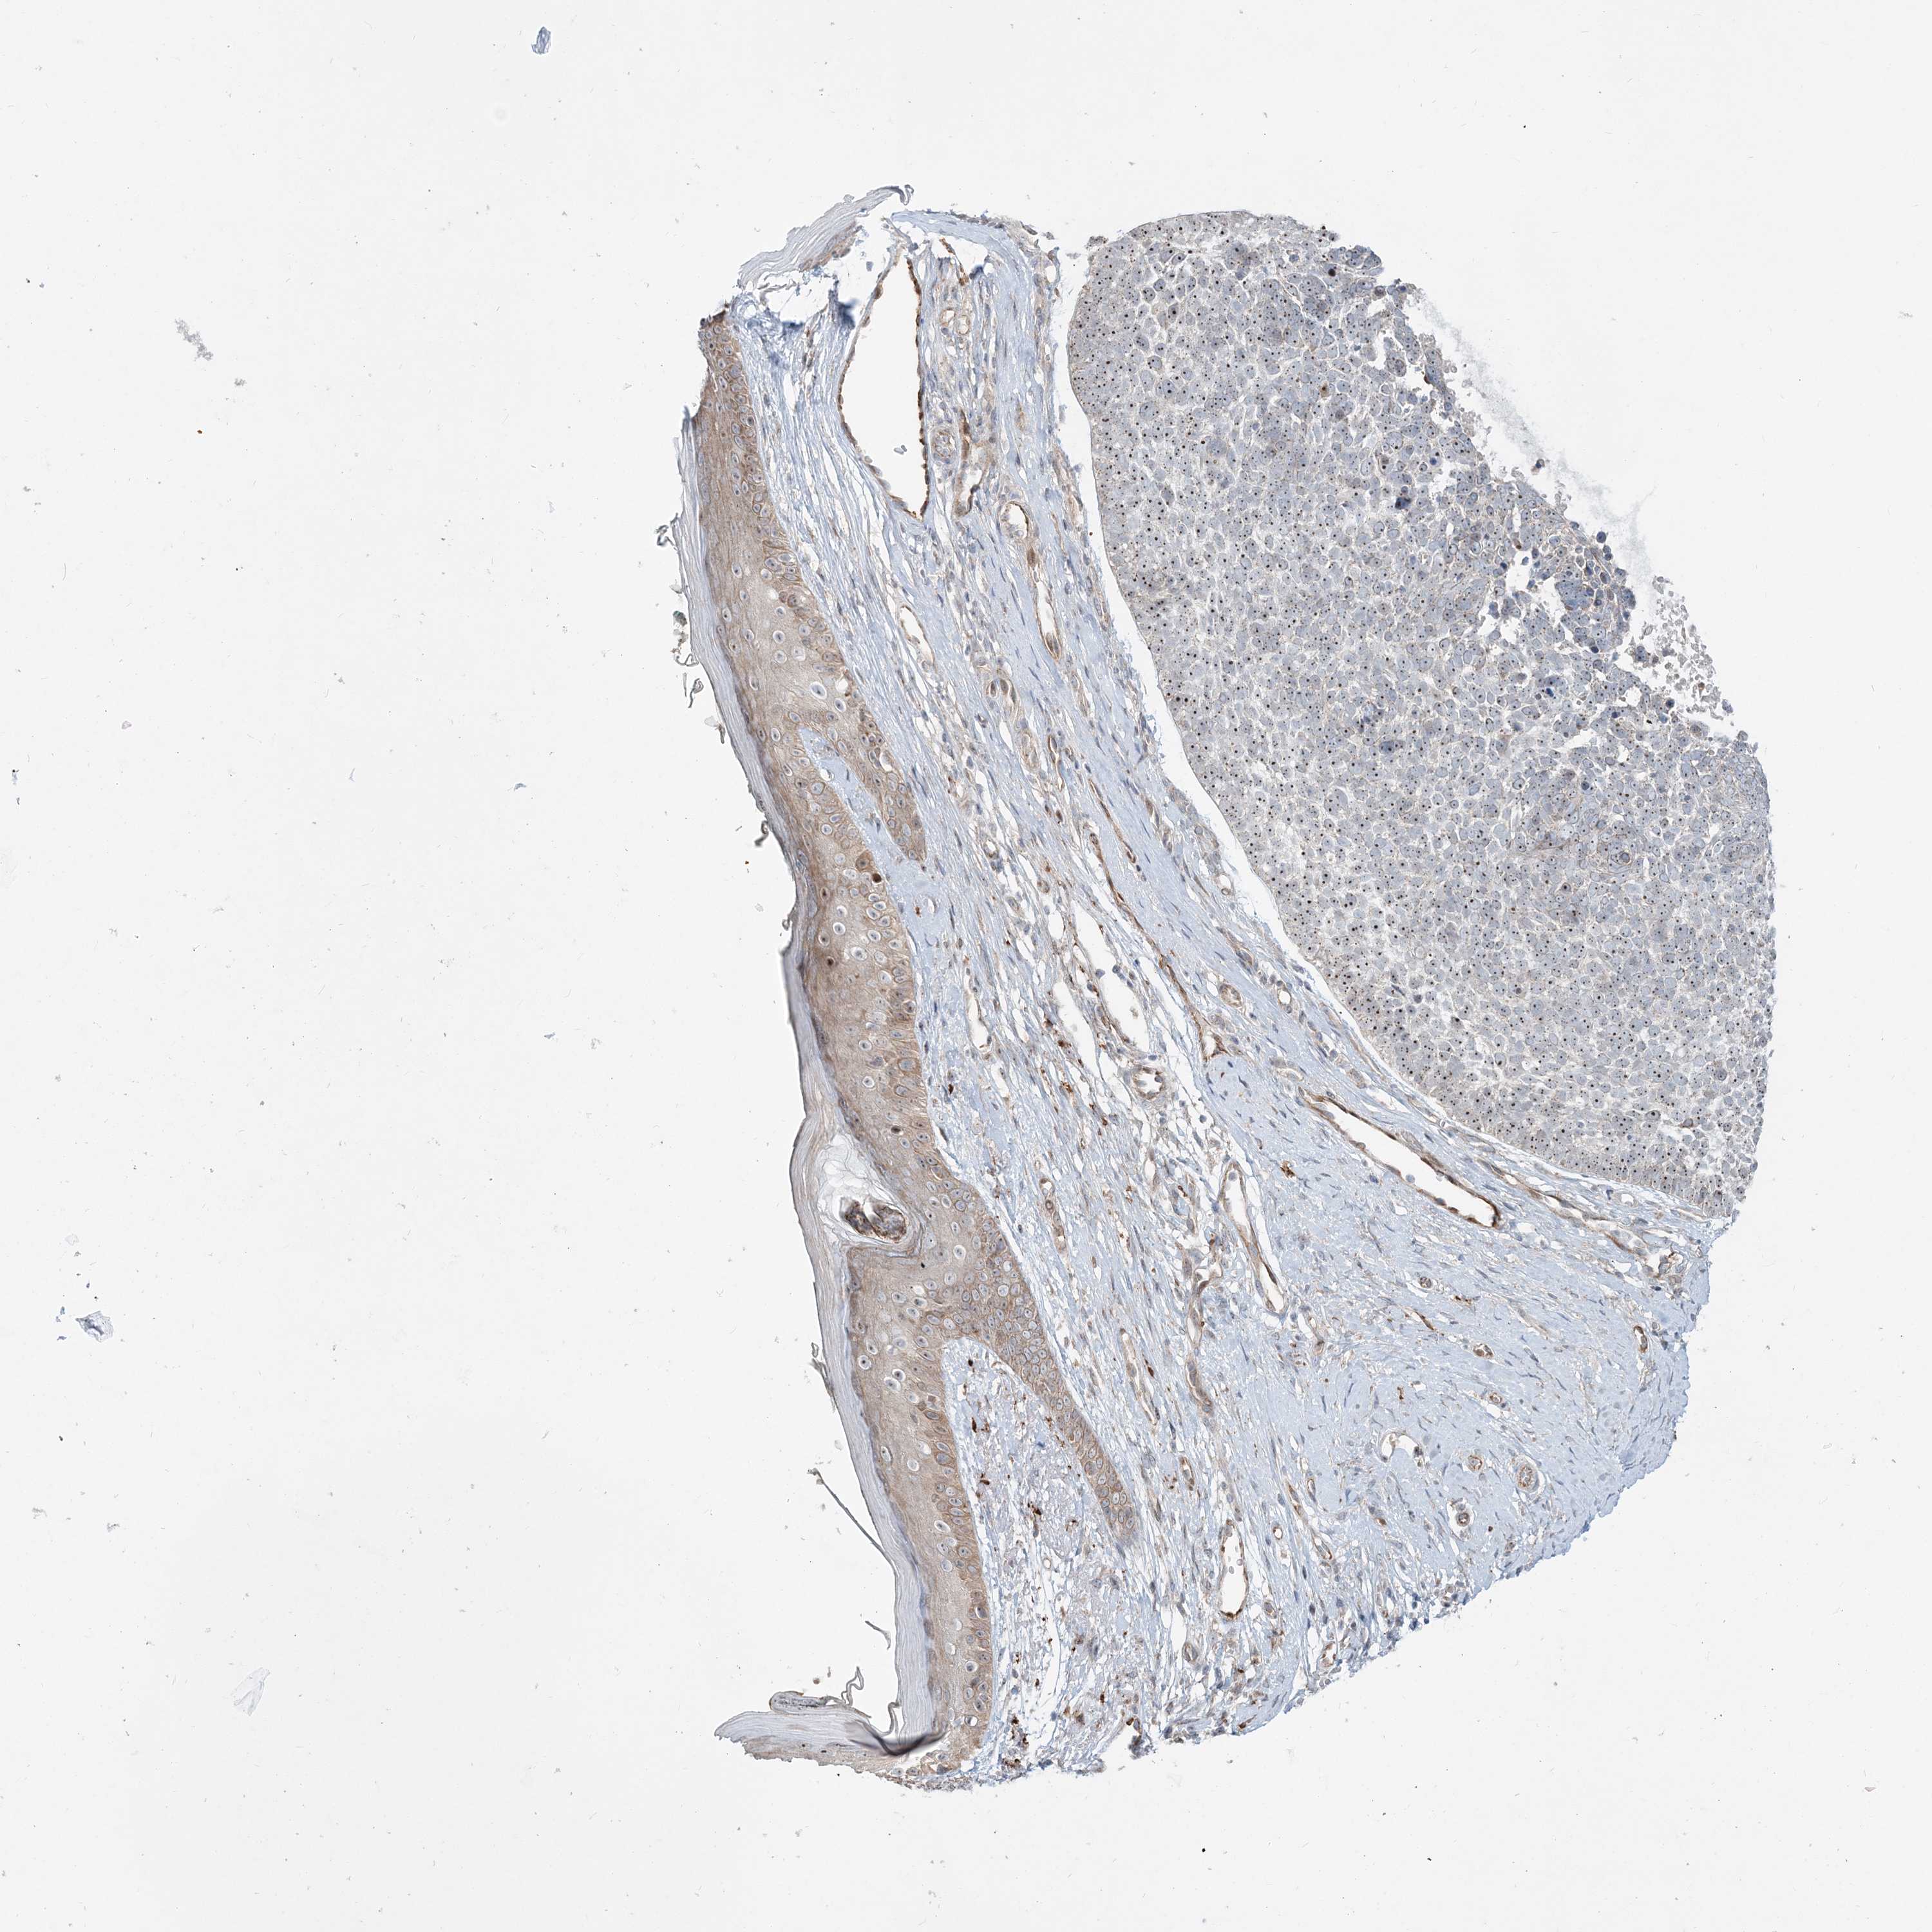

SKIN CANCER - Protein expressioni

A mouse-over function shows sample information and annotation data. Click on an image to view it in a full screen mode. Samples can be filtered based on level of antibody staining by selecting one or several of the following categories: high, medium, low and not detected. The assay and annotation is described here.

Antibody staining in the annotated cell types in the current human tissue is reported as not detected, low, medium, or high, based on conventional immunohistochemistry profiling in selected tissues. This score is based on the combination of the staining intensity and fraction of stained cells.

Each image is clickable and will lead to virtual microscopy that enables deeper exploration of all samples and also displays staining intensity scores, fraction scores and subcellular localization as well as patient and tissue information for each sample.

Antibody HPA036508

Squamous cell carcinoma, metastatic, NOS

Squamous cell carcinoma, NOS